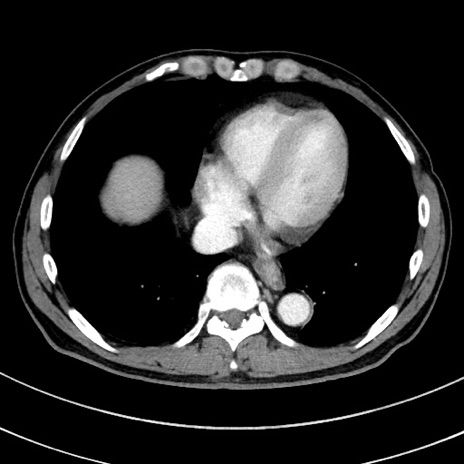

冠状断像

症例8(横断像)

【症例】 60歳代男性

【主訴】 黒色吐物

【現病歴】 4日前から嘔気自覚、2日前の朝食後にも嘔気あり、自分で手で嘔吐反射起こし嘔吐したところ血が混ざっていたため受診。

【既往歴】 5年前汎発性腹膜炎を伴う急性虫垂炎で手術、高血圧、前立腺肥大症、高脂血症

【身体所見】 腹部正中に手術癩痕あり 腹部平坦・軟圧痛なし膨満感あり

【データ】WBC 8400、CRP 4.54